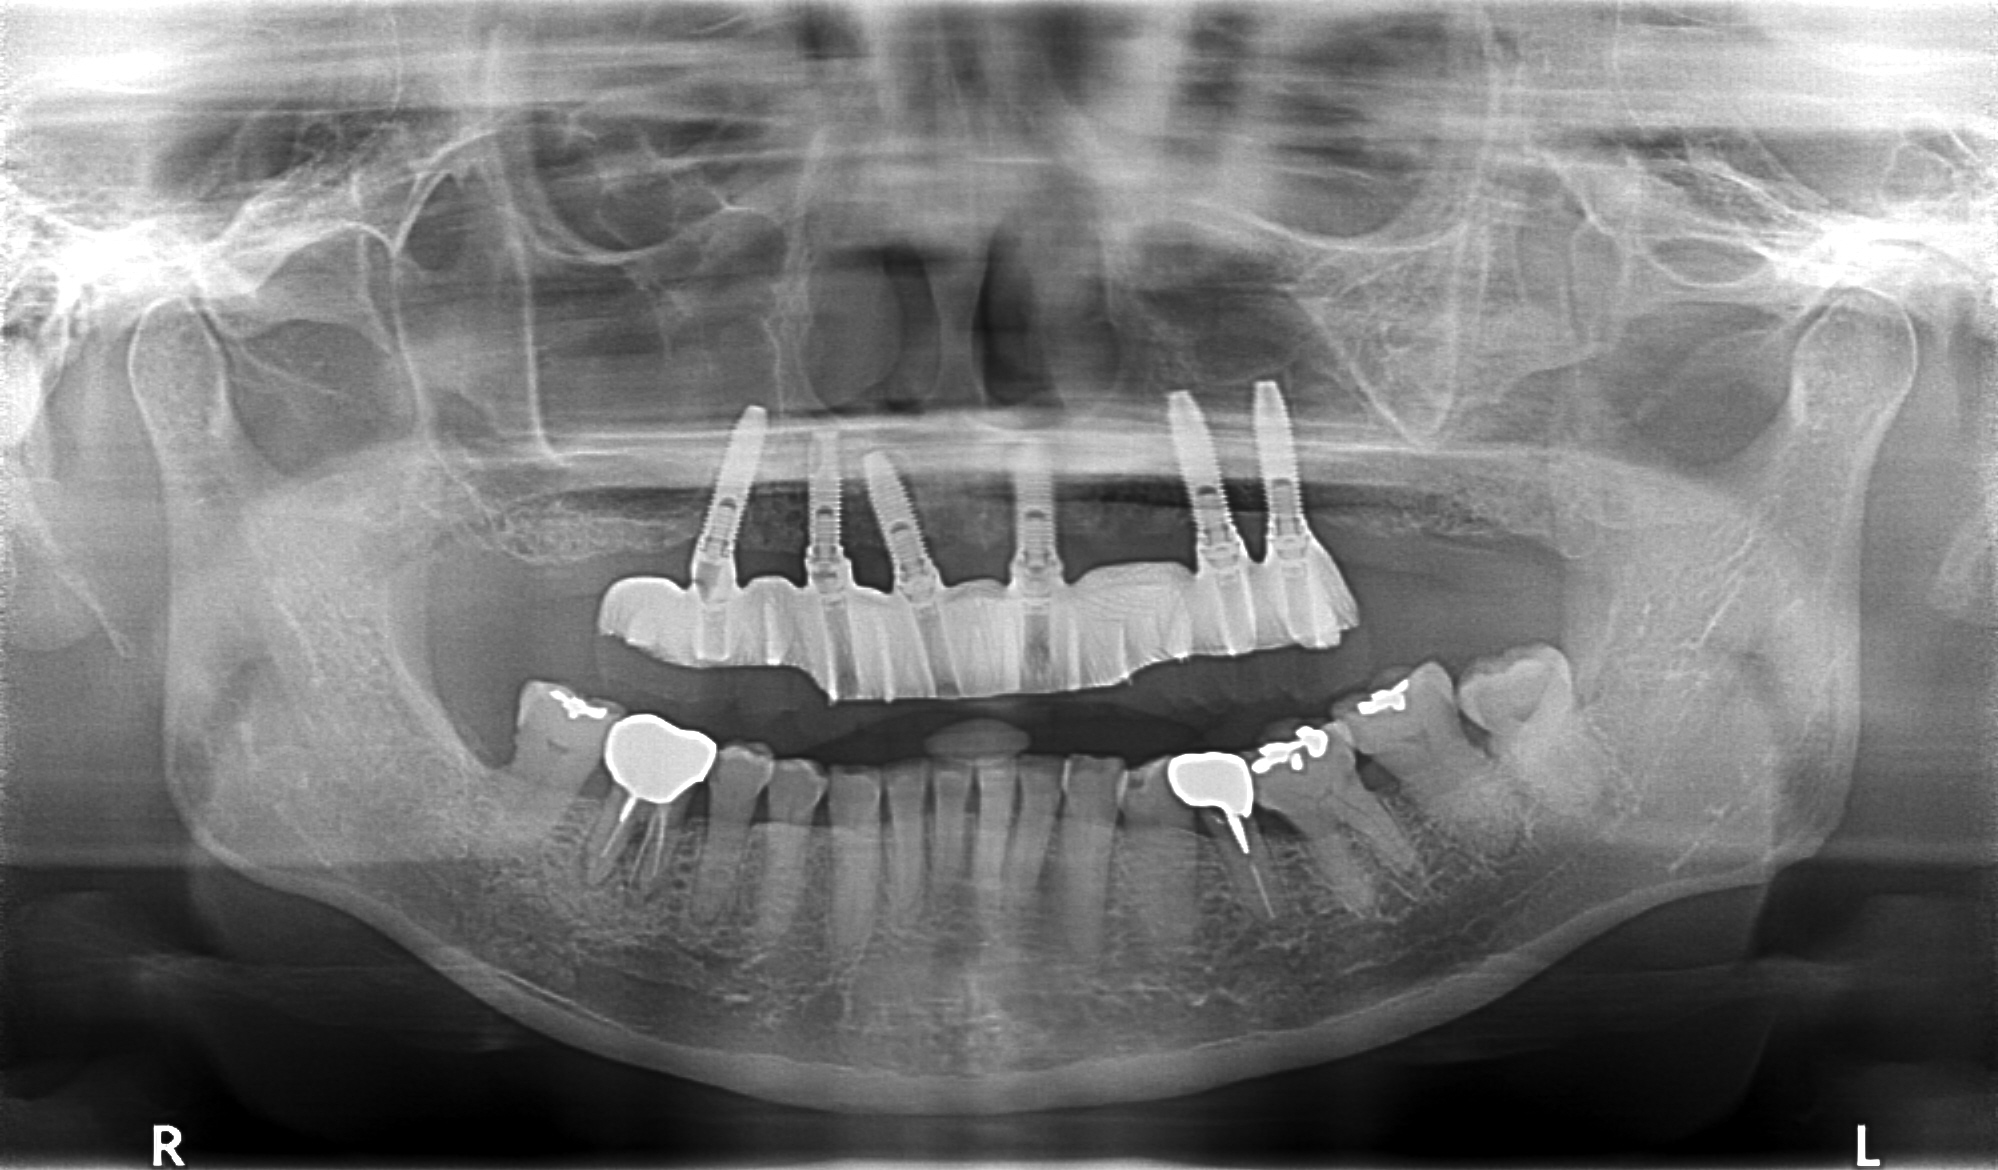

症例紹介

- 主訴

- 入れ歯が合わない。食べにくい。人生を豊かにしたい。

- 処置内容

- 上顎4本で12歯(オールオン4)、下顎4本5歯。

上下抜歯即時埋入、即時荷重(手術当日にインプラントの上に仮歯装着)

- 治療費用

- 上顎:約290万(税込)、下顎:約210万円(税込)

- 治療期間・通院回数

- 上顎:9か月/9回

下顎:6か月/7回

- リスク

- 術後の腫れ、痛み(ピークは3日後、1週間で軽減)

上部構造物、仮歯の破折、人工歯根脱落リスクがあります